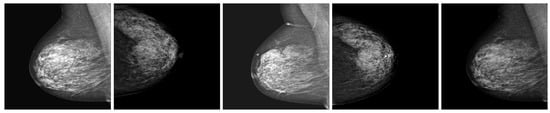

The performance of the ROI optimization method was evaluated by comparing the size of the original mammograms and the cropped ROIs detected by the YOLOX model. Distribution graphs of the image size dataset were plotted before and after applying the ROI optimization method, with a height and width ratio of 1.018, as depicted in Figure 4. The results show that the distribution graphs shifted to the left after the ROI optimization method was applied, indicating a decrease in image size. The mean image size of data decreased by 76.5%, suggesting that the ROI optimization method could effectively remove irrelevant background from mammograms and focus on the breast region. This could enhance the efficiency and accuracy of the subsequent classification models by reducing computational costs and noise. Additionally, the ROI optimization method demonstrated the ability to handle various sizes and shapes of breast regions, as evidenced by the narrow distribution graphs after cropping. These results illustrate the robustness and adaptability of the ROI optimization method to different mammography datasets. Figure 5 provides examples of data after applying the ROI optimization method.

Figure 5.

Examples of data after applying ROI optimization method.